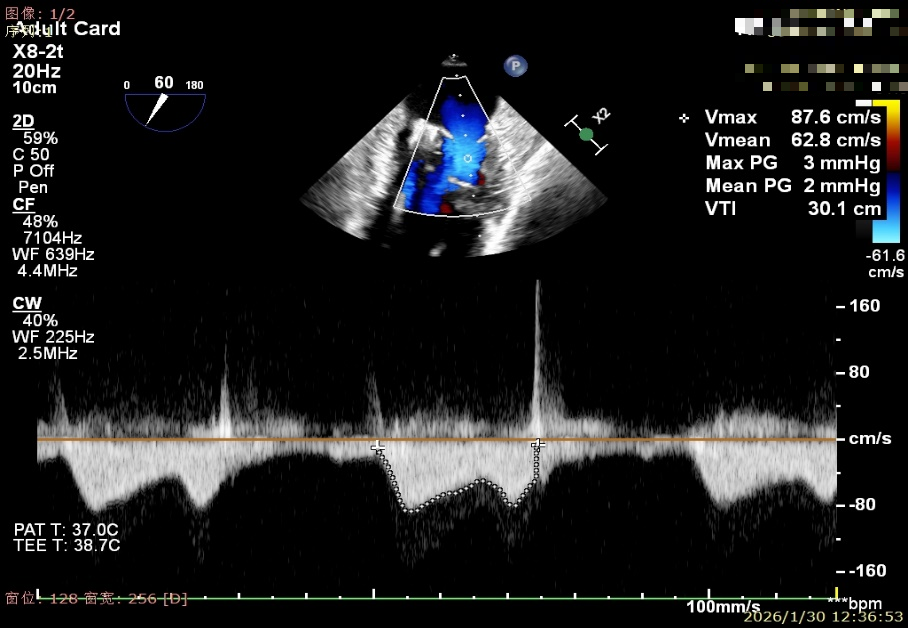

植入两枚夹子后二尖瓣平均跨瓣压差2mmHg

建立右侧股静脉入路,在食道超声引导下进行房间隔穿刺,获得穿刺高度4.1cm,交换Super Stiff超硬导丝至左上肺静脉,使用血管鞘扩张股静脉后,沿超硬导丝送入可操控导引导管(SGC)至左房,将第一枚二尖瓣夹输送系统(CDS-XTR)送入左心房。送入夹子过程中为避免碰到左房组织完成Straddle“骑跨”,顺利完成Straddle并将夹子打弯至二尖瓣环水平。接下来为避免发生缠绕在1区进行轨迹测试,使夹子的运动轨迹指向心尖。在心房侧打开夹臂,调整夹臂方向指向12点-6点方位,与二尖瓣对合缘垂直。完成调整后将夹子移动至3区位置,将二尖瓣夹关紧后缓慢送入左心室。在左室打开夹子重新确认Orientation。准确成功捕捞3区前叶脱垂及反流区域,确认瓣叶瓣尖稳定插入夹臂后,Gripper Down,观察到明显Bouncing后,关紧夹臂予以夹合,夹子内侧反流消失,夹子外侧还有残余脱垂及中量反流。考虑瓣叶长度11mm以上,瓣口面积足够,决定在外侧Side by Side再植入一枚XTR,植入两枚XTR后活动稳固,反流降至Trace。术后肺静脉逆流消失,二尖瓣平均跨瓣压差2mmHg。